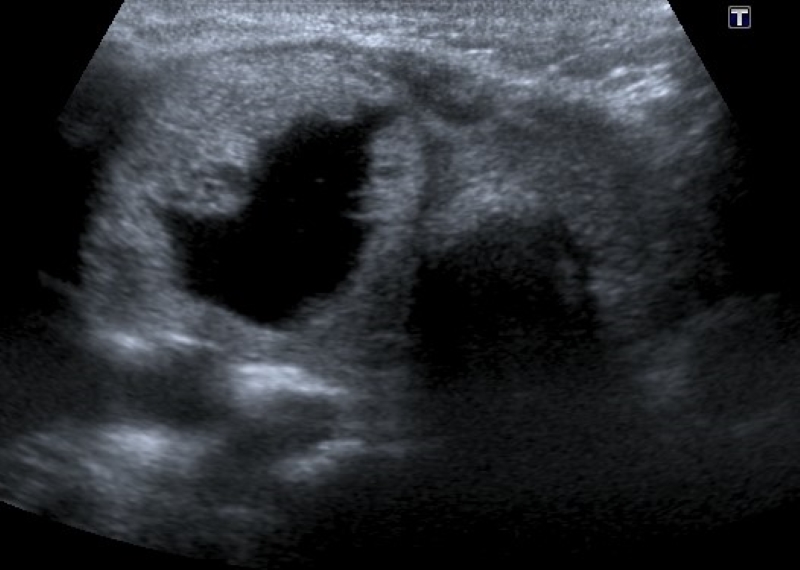

Describe el componente interno del nódulo, identificando la presencia de contenido sólido (Fig. 1) o quístico (Fig. 2), y en los casos de nódulos mixtos (Fig. 3) la proporción de cada uno (predominantemente sólido/ predominantemente quístico). Cuando se evalúa un nódulo parcialmente quístico es importante caracterizar su componente sólido indicando además si tiene localización central o periférica (esta última podría asociarse con mayor riesgo de malignidad)13.

Los nódulos completamente quísticos son considerados benignos2,14,15) y los sólidos se asocian mayormente a malignidad15,16, pero hay descriptos nódulos sólidos benignos, como así también nódulos confirmados como CPT con componente mixto2,15,17.